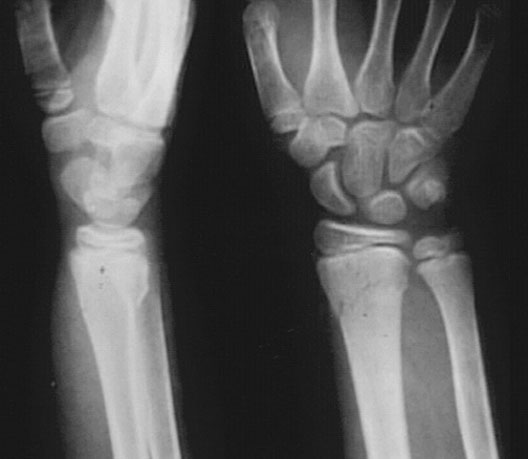

Colles Fracture of the Wrist

1. Radial Growth Plate

2. Colles Fracture